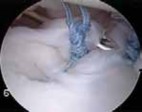

The foundation of a successful arthroscopic stabilization is the meticulous mobilization of the capsulolabral complex. In chronic cases, the torn labrum and IGHL frequently heal in a medially displaced position along the anterior glenoid neck (the ALPSA lesion). Using a combination of arthroscopic elevators, rasps, and electrocautery, the surgeon must aggressively liberate this tissue from the scapular neck. The release must extend inferiorly to the 6 o'clock position to adequately mobilize the inferior capsule. Once the tissue is freed and can be easily reduced to the articular margin, the anterior glenoid neck is lightly decorticated using a motorized burr or rasp. This critical step removes fibrous tissue and exposes bleeding cancellous bone, creating an optimal biological environment for robust soft-tissue healing.